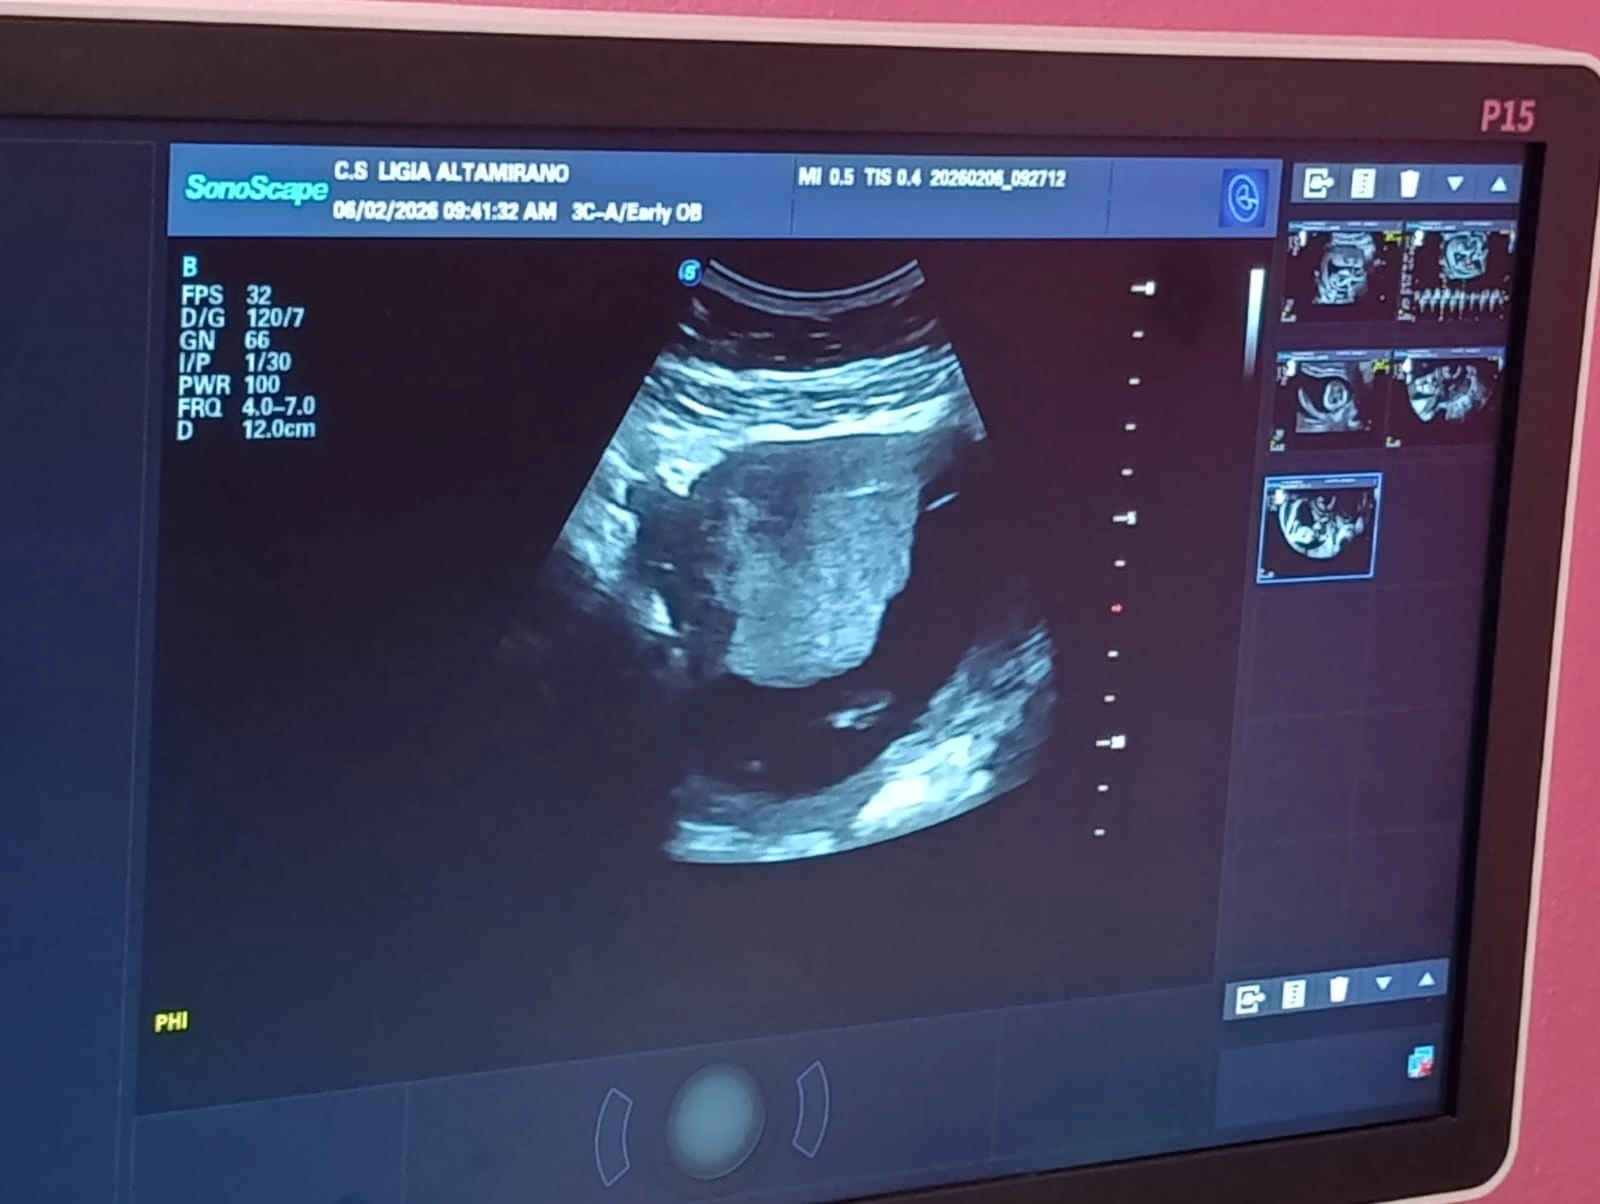

En el Centro de Atención a la Mujer Doctora Ligia Altamirano, mujeres embarazadas del departamento de Managua recibieron atención médica integral en la feria de salud realizada con el fin de disminuir complicaciones tanto maternas como neonatales.

“Este estudio aplica la realización de un tamizaje del primer trimestre que consiste en la realización de ultrasonido obstétrico, en donde se valora la edad gestacional del bebé, y también se utiliza el tamizaje de arterias uterinas para valorar el riesgo a desarrollar preclampsia en la embarazada y, por último, lo que es la medición de la longitud cervical, que ayuda a valorar las pacientes que tienen un alto riesgo de desarrollar un parto pretérmino”, aseguró García.